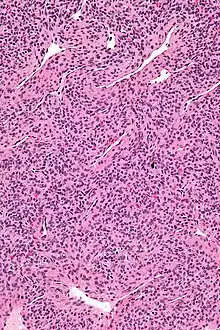

| Micrograph of a myopericytoma. H&E stain. | |

Myopericytoma is a rare perivascular soft tissue tumour. It is usually benign and typically in the distal extremities.[1]